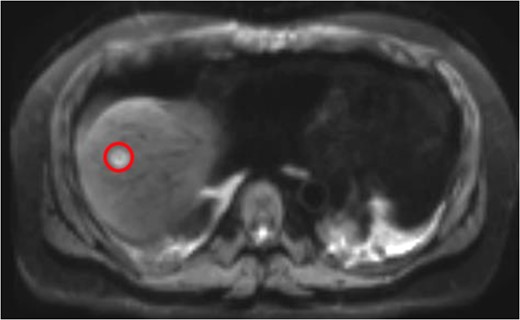

Neoadjuvant therapy was completed 1 month before surgical intervention. The patient underwent bilateral ureteral stents placement and an exploratory laparotomy in the lithotomy position. Intraoperative ultrasonography localized the tumor without showing any unexpected lesions. A right extended hepatectomy proceeded in the standard manner (Figs 3 and 4).

The colon was fully mobilized, and the mesentery was transected with high ligation of the ileocolic and middle colic pedicles. Because of the patient’s inferior mesenteric artery stump bulky disease, the surgeons performed a complete para-aortic lymphadenectomy and en bloc resection. The abdominoperineal resection was performed without incident. A pelvic drain was placed. His 15-day hospitalization was complicated by anemia requiring transfusions, lower-extremity deep vein thrombosis and prolonged ileus.